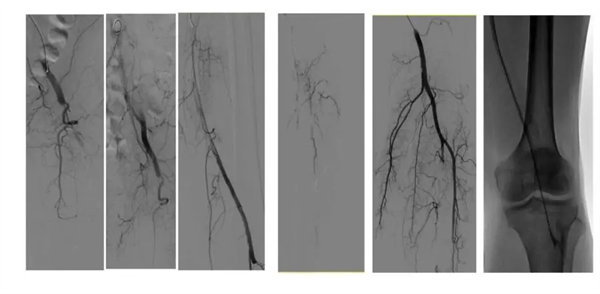

積極行術前準備,急診在局麻下行“左下肢動脈造影術+血栓抽吸術+置管溶栓術”, 髂動脈造影提示左側髂外動脈閉塞,局部大量血栓形成,反復抽吸后股淺動脈、腘動脈開通,膝下動脈部分開通,遂留置溶栓導管動脈溶栓治療2天,動態觀察下肢動脈血運及穿刺鞘管情況。